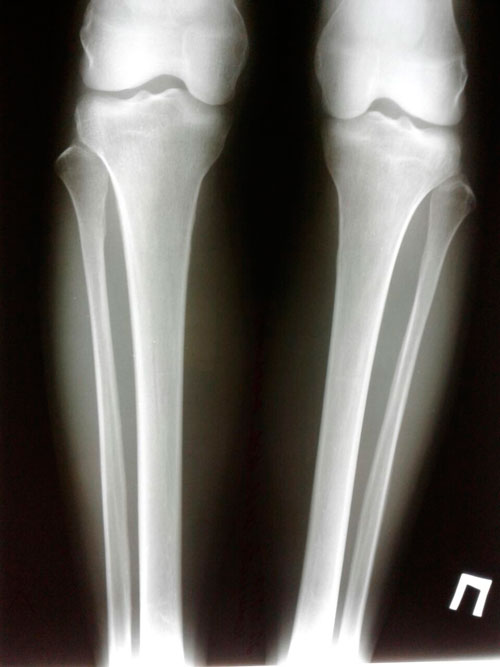

Исходник - 40 лет.

Дата операции 28.09.2017г.

2-я ротация.

IMG-20170927-WA0009.jpg

IMG-20170927-WA0010.jpg

IMG-20170927-WA0014.jpg